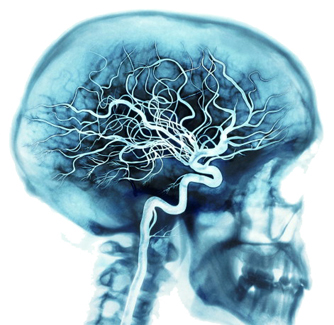

2. Zasilanie mózgu

Odżywianie mózgu odbywa się poprzez rozbudowaną sieć naczyń krwionośnych.

Z każdym uderzeniem serca arterie krwionośne dostarczają do mózgu około 20-25 procent krwi obecnej w organizmie. Miliardy komórek mózgowych pobierają z krwi prawie 20 procent transportowanego tlenu oraz substancji odżywczych.

Przy intensywnej aktywności umysłowej zapotrzebowanie mózgu może wzrosnąć do 50 procent tlenu i substancji odżywczych obecnych we krwi.

Na sieć naczyń krwionośnych składają się żyły, arterie oraz naczynia włosowate.